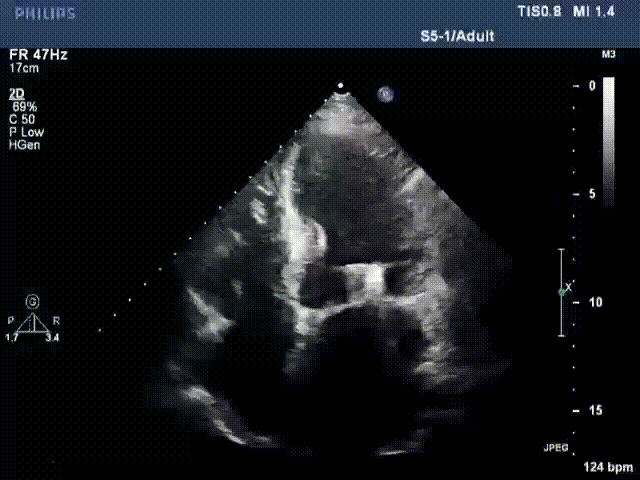

術前超聲提示二尖瓣重度反流

術后超聲顯示二尖瓣反流消失,瓣膜夾穩定

接受治療的是一例器質性重度二尖瓣反流(DMR)患者,主訴“反復活動后胸悶,氣促3年余”。術前超聲顯示,雙房增大,二尖瓣脫垂伴重度反流,輕度三尖瓣反流,輕度肺高壓,升主動脈增寬。手術經股靜脈-房間隔入路,采用全身麻醉插管,在TEE和DSA引導下完成房間隔穿刺。置入JensClip瓣膜夾系統后,在左房調整瓣膜夾的位置和軸向,后進入左室,在TEE引導下捕捉二尖瓣前后瓣葉,并關閉瓣膜夾。經TEE反復確認手術效果后最終鎖定并釋放瓣膜夾。術后即刻超聲顯示瓣膜夾位置穩定,功能良好,術前二尖瓣反流4+,術后0反流,肺靜脈逆流和左房壓都顯著好轉,手術圓滿成功(以上數據都來源于醫院的臨床記錄)。術后患者狀態良好,目前已安排出院。